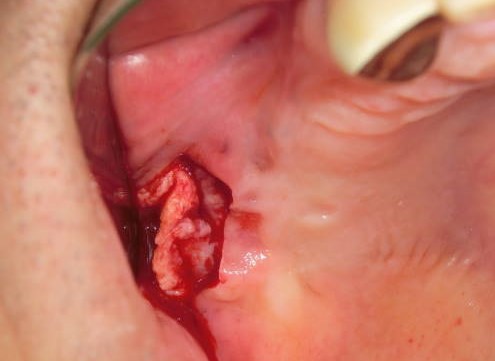

(2)後臼歯隆起部の外骨症

とがった骨の鋭縁に入れ歯が当たって長期間痛みが続いていました。

鋭縁分の骨を削って平にしたら、痛みは完全に無くなりました。

局所麻酔で20分ほどの処置でした。